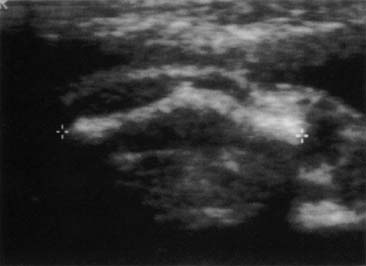

It is well known, however, that abuse during pregnancy poses significant risks for both mother and fetus. The adverse effects of abuse during pregnancy result from either direct or indirect causes. Direct causes of adverse perinatal effects include abruptio placentae; fetal fractures; rupture of the maternal uterus, liver, or spleen; maternal pelvic fractures; and antepartum hemorrhage (Fig. 3).10 Indirect effects include maternal stress, isolation of the mother and inadequate health care, behavioral risks such as substance use, and inadequate maternal nutrition (either secondary to emotional factors or as part of the abuse cycle). For the practicing obstetrician/gynecologist, pregnancy presents a unique opportunity to form a partnership with a woman for the identification and assessment of IPV. Pregnancy may motivate women to seek help from abusive relationships. It may also be the only time that a woman seeks medical attention. The fetal consequences of the abuse may be the factor that motivates the woman to take steps to remove herself from the abusive situation.

Fig. 3. Fractured fetal femur secondary to IPV.